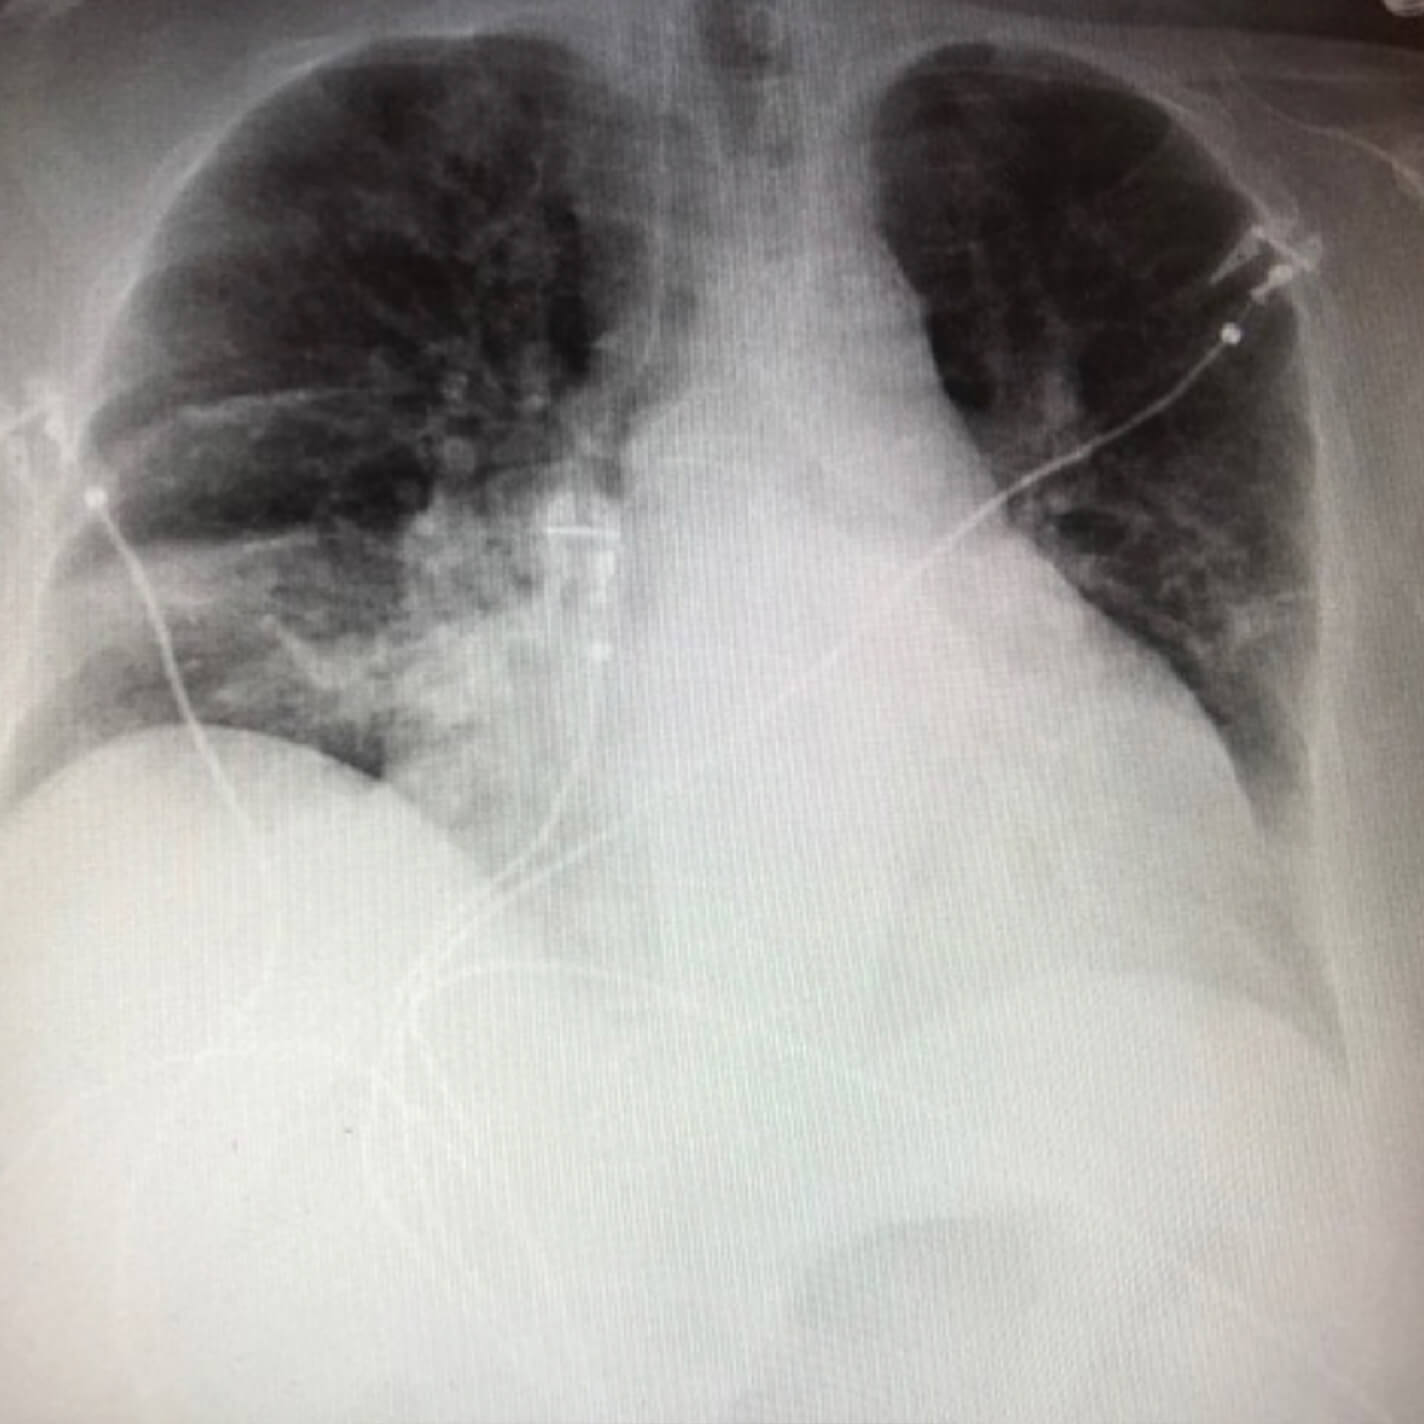

Follow-up chest x-ray (after 28 days)

After image of a follow-up chest x-ray (after 28 days)

Appreciable improvement in respiratory status and equivocal chest x-ray; decision made to continue treatment of bacterial pneumonia. Patient given NUZYRA 300 mg loading dose twice daily